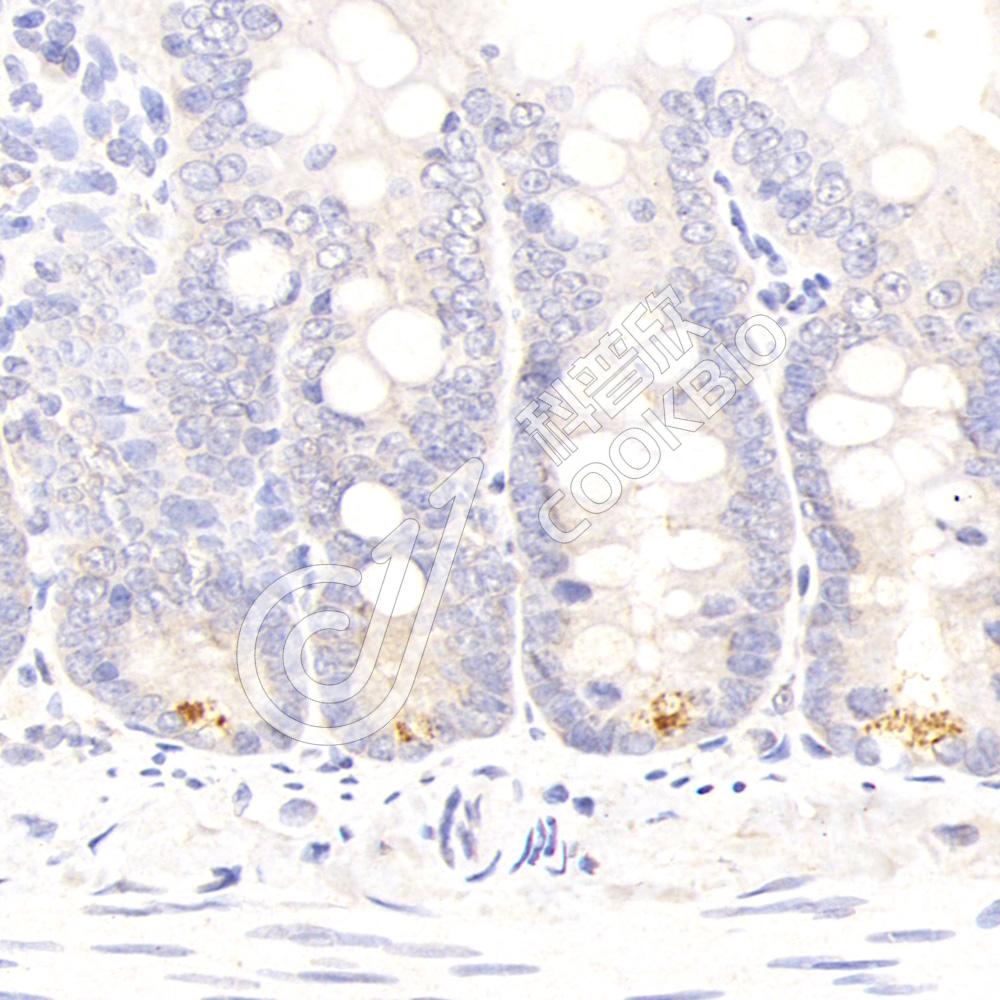

IHC检测Secretory phospholipase A2蛋白(货号 K1341031).

样品: 小鼠小肠, 4%多聚甲醛 (货号KSG1101) 固定12-24小时.

抗原修复: 柠檬酸抗原修复液(干粉, pH 6.0) (KSG1201), 98℃, 20分钟.

—抗: 1: 300稀释, 4℃ 孵育过夜.

二抗: S-vision免疫组化多聚二抗(山羊抗兔),即用型 (货号KB3906), 室温孵育20分钟.

样品: 大鼠小肠, 4%多聚甲醛 (货号KSG1101) 固定12-24小时.